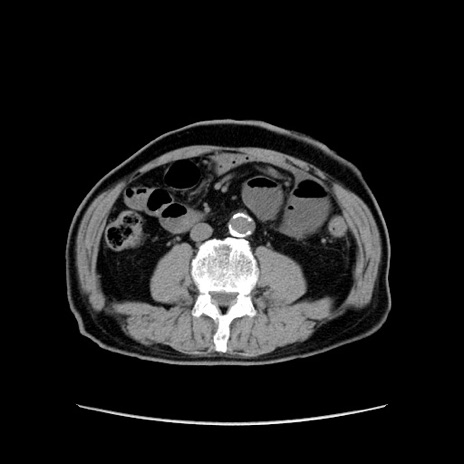

症例24(横断像)

【症例】80歳代男性

【主訴】左側腹部痛、嘔吐

【現病歴】本日早朝より左腹部に痛みあり。昼頃嘔吐認めたため、救急要請。

【既往歴】直腸癌(Mile手術)、胆摘

【身体所見】意識清明、BT 35.9℃、BP 221/93mmHg、SpO2 97%(RA) 、腹部:左ストーマ周囲に限局性の腹部膨隆あり。 膨隆部自発痛・圧痛あり・軟。

【データ】WBC 7700、CRP 0.09